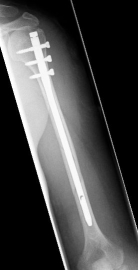

Picture: In the above pictures, a slightly shifted subcapital humeral fracture was internally splinted using intramedullary nail. The left picture is a follow-up examination half a year after the accident and shows the complete healing of the fracture with correct position of the bone.